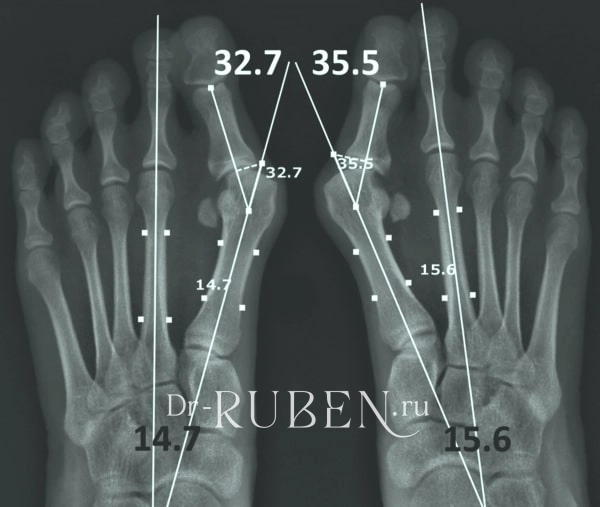

Медицинские решения: Операция по коррекции Hallux valgus